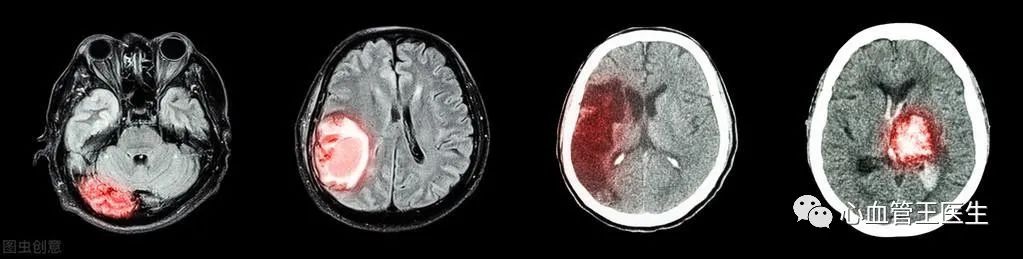

如果出现这些表现,说明已经中风,当然是脑出血还是脑梗死,必须进一步脑CT或核磁才能确诊。